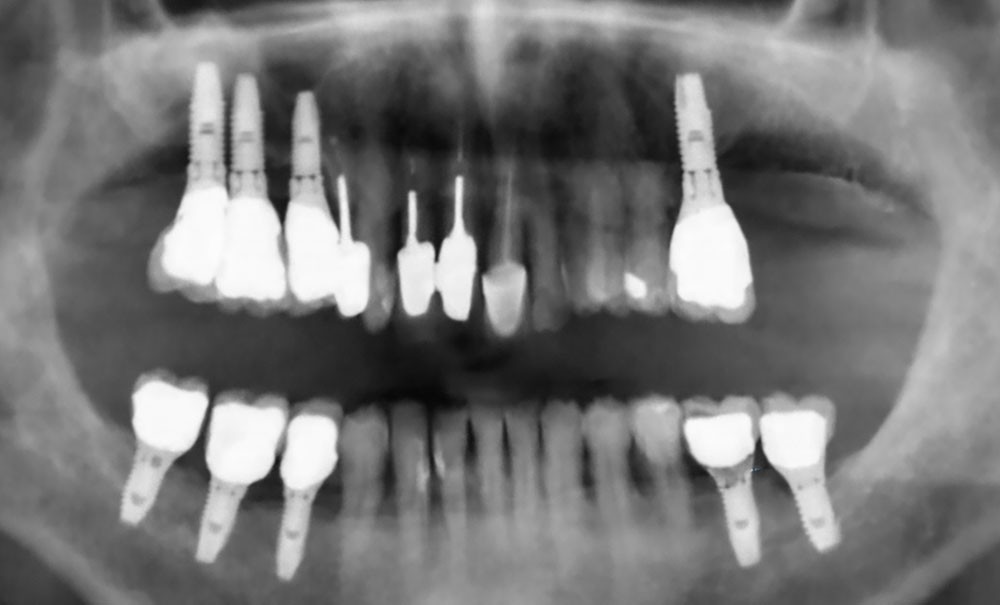

• réaliser un examen clinique et radiologique complet ;

• éliminer les foyers infectieux ;

• stabiliser l’état bucco-dentaire.